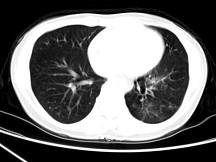

问题 女,30岁,咳痰,咯血,请结合影像图像选择最可能的诊断为 ( )

选项 A、间质性肺炎 B、肺结核 C、支气管扩张并感染 D、支气管囊肿 E、肺部感染

答案 C